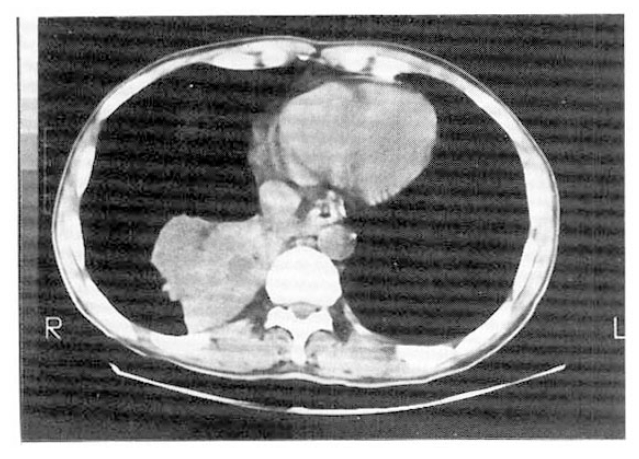

Fig. 2.

Computed tomographic scan of the chest showing a mass with soft tissue density in the posterior segment of the right lower lobe.

A 41-year-old male was admitted with fever, dry cough and pleuritic chest pain for 10 days. He had always considered his health to be good except that he had a subtotal gastrectomy due to peptic ulcer bleeding 20 years before admission. On examination, his blood pressure was 130/80 mmHg, pulse rate was 90/min and body temperature was 100.8 °F. Breathing sounds were diminished over the lower half of the right posterior chest. Laboratory data included a hemoglobin of 13g%, hematocrit of 44%, white blood count of 12,400/mm3 with 60% neutrophil, 35% lymphocyte, 4% monocyte and 1% eosinophil. IgE was 20 IU/ml. No pathogen was found in the smear and culture of the sputum. Immediate skin test to Aspergillus antigen was nonreactive. Serum precipitins to Aspergillus fumigatus were positive. Chest roentgenogram showed a well-defined mass in the posteromedial portion of the right lower lobe (Fig. 1). The pulmonary perfusion scan using 99mTc-macroaggregate albumin showed a perfusion defect in the right lower lung field, corresponding to the lesion in the chest roentgenogram. A computed tomographic scan of the chest showed a mass with soft tissue density in the posterior segment of the right lower lobe (Fig. 2). CT-guided biopsy specimens from the lesion showed aggregations of hyphae of Aspergillus.